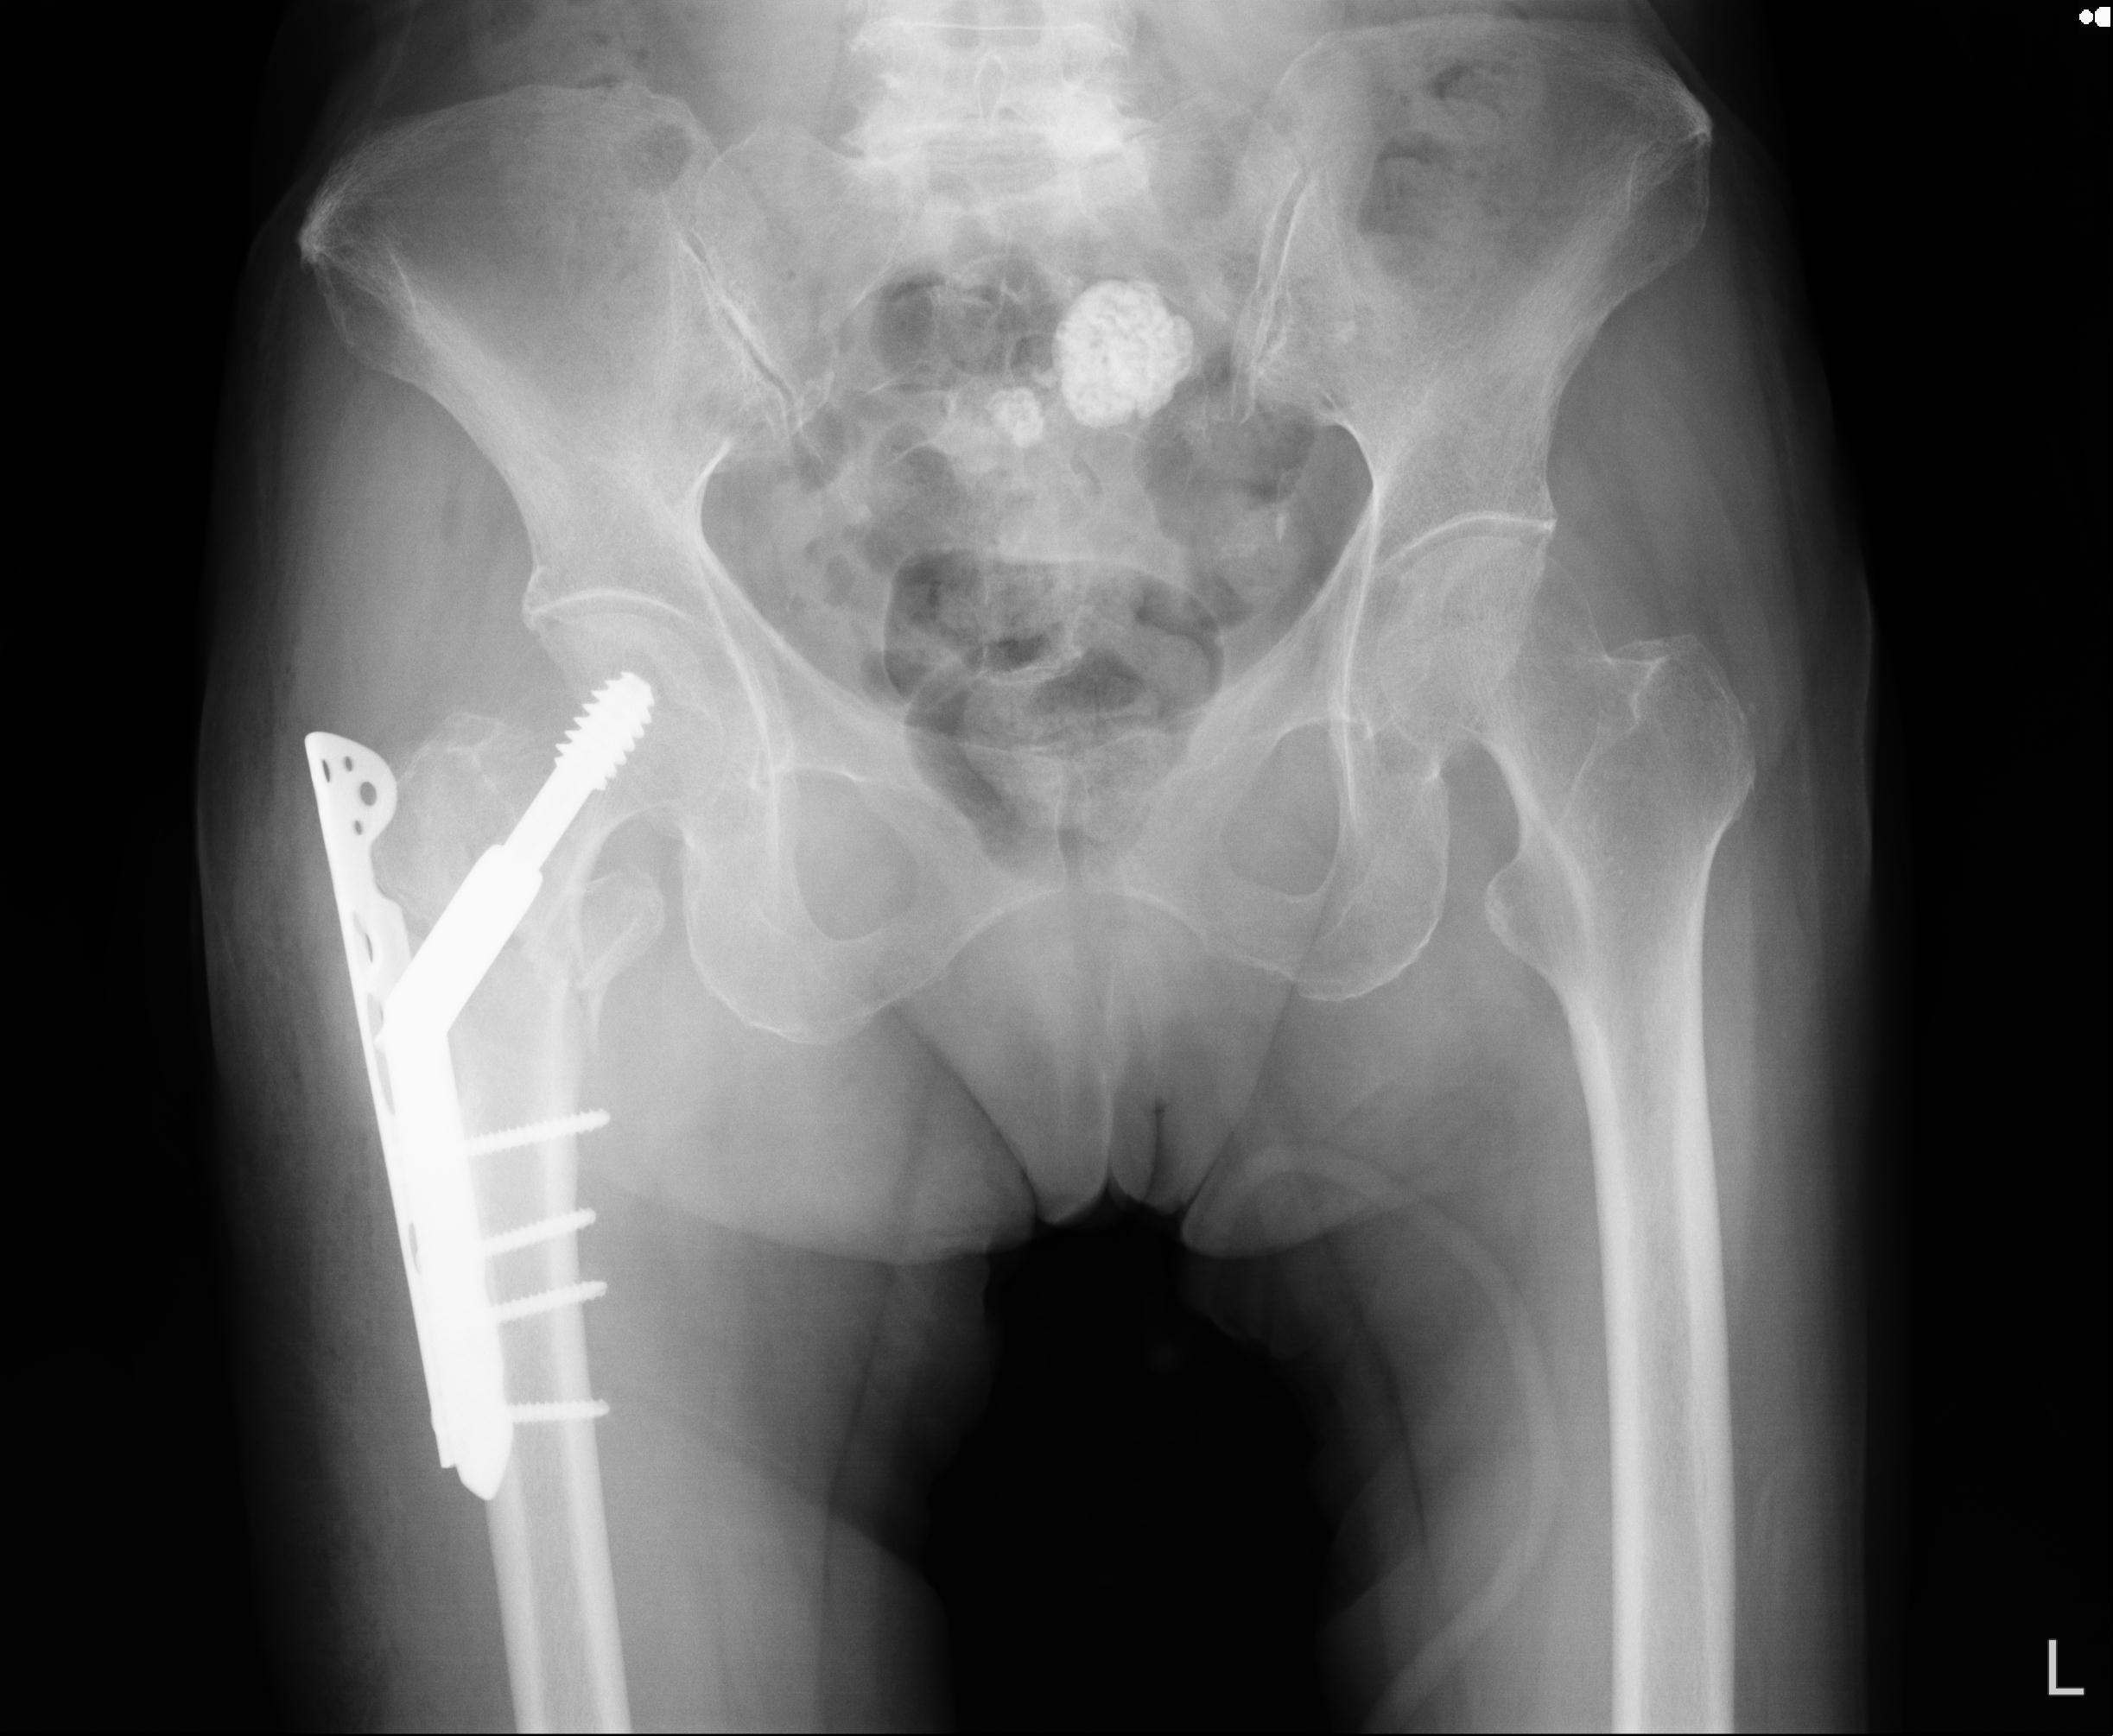

46666 1/28 両股正面+軸と 1/26 右手関節 2R 76歳女性 右転子部骨折